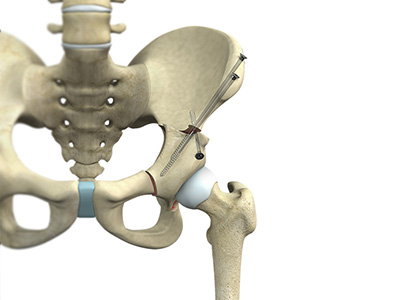

The hip joint is the junction where the hip joins the leg to the trunk of the body. It is comprised of two bones: the thigh bone or femur and the pelvis which is made up of three bones called ilium, ischium, and pubis. The ball of the hip joint is made by the femoral head while the socket is formed by the acetabulum. The Acetabulum is a deep, circular socket formed on the outer edge of the pelvis by the union of three bones: ilium, ischium, and pubis. The lower part of the ilium is attached by the pubis while the ischium is considerably behind the pubis. The stability of the hip is provided by the joint capsule or acetabulum and the muscles and ligaments which surround and support the hip joint.

The head of the femur rotates and glides within the acetabulum. A fibrocartilagenous lining called the labrum is attached to the acetabulum and further increases the depth of the socket.

The femur or thigh bone is one of the longest bones in the human body. The upper part of the thigh bone consists of the femoral head, femoral neck, and greater and lesser trochanters. The head of the femur joins the pelvis (acetabulum) to form the hip joint. Next, to the femoral neck, there are two protrusions known as greater and lesser trochanters which serve as sites of muscle attachment.